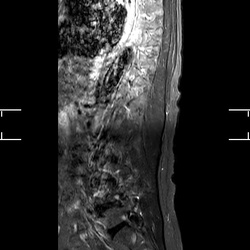

MRI_MobiView_Sag_STIR_TSE_503

21 photos

MRI_MobiView_Sag_T1W_TSE_603

21 photos

MRI_MobiView_Sag_T2W_TSE_403

21 photos